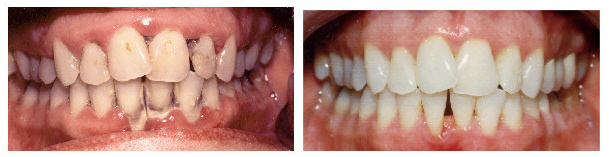

Травматический периодонтит: фото до и после